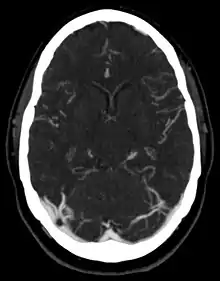

التصوير المقطعي (المحوسب)

مقالة مفصلة: الأشعة المقطعية

يستخدم التصوير المقطعي الاشعة السينية مع خوارزميات الحوسبة لتصوير الجسم. في الأشعة المقطعية، يتدفق أنبوب الأشعة السينية المقابل لكاشف الأشعة السينية (أو أجهزة الكشف) في جهاز على شكل حلقة حول المريض، مما ينتج صورة مقطعية مستحدثة بالكمبيوتر (توموغرام). يتم الحصول على الأشعة المقطعية في الطائرة المحورية ، مع الصور الاكليلية والسهلية التي تنتجها إعادة بناء الكمبيوتر. غالبًا ما تُستخدم عوامل الإشعاع الراديوي مع التصوير المقطعي المحوسب للتشديد المُحسَّن للتشريح. على الرغم من أن الصور الشعاعية توفر دقة مكانية أعلى ، إلا أن الأشعة المقطعية يمكن أن تكتشف اختلافات أكثر دقة في توهين الأشعة السينية (دقة التباين الأعلى). الأشعة المقطعية تعرض المريض إلى إشعاع مؤين أكثر بكثير من التصوير الشعاعي.

تستخدم أجهزة القياس المتعددة الحلزونية الحلزونية 16 أو 64 أو 254 أو أكثر من أجهزة الكشف خلال الحركة المستمرة للمريض من خلال شعاع الإشعاع للحصول على صور دقيقة في وقت قصير للاختبار. مع الإدارة السريعة للتناقض الوريدي خلال الاشعة المقطعية ، يمكن إعادة بناء هذه الصور التفصيلية الدقيقة في صور ثلاثية الأبعاد (ثلاثية الأبعاد) للشرايين السباتية أو الدماغية أو الشرايين التاجية أو غيرها من الشرايين.

أدى إدخال التصوير المقطعي في أوائل السبعينيات إلى ثورة في علم الأشعة التشخيصية من خلال تزويد الأطباء بصور لبنى تشريحية حقيقية ثلاثية الأبعاد. أصبح التصوير المقطعي اختبارًا في اختيار بعض الحالات العاجلة والطارئة ، مثل النزف الدماغي ، الانسداد الرئوي (الجلطات في شرايين الرئتين) ، تشريح الأبهر (تمزيق جدار الأبهر)، التهاب الزائدة الدودية، التهاب الرتج ، وعرقلة الكلى الحجارة. أدت التحسينات المستمرة في تقنية التصوير المقطعي المحوسب، بما في ذلك سرعة المسح الضوئي وتحسين الدقة ، إلى زيادة دقة وفائدة المسح المقطعي ، الأمر الذي قد يفسر بشكل جزئي زيادة الاستخدام في التشخيص الطبي.